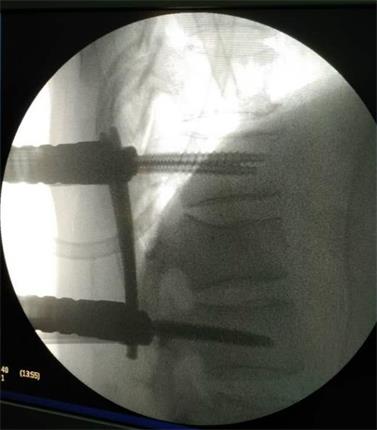

在成功的完成手術(shù)之后,使用過(guò)國內外眾多品牌微創(chuàng )系統的主刀醫生對該PINE III也給出了這樣的評價(jià):“操作真的方便太多,而且對壓縮骨折的復位效果也遠超同類(lèi)產(chǎn)品,以后就用這個(gè)了!”

該系統是針對胸腰椎后路微創(chuàng )手術(shù)設計的經(jīng)皮內固定系統,采用“自通道”設計,置釘時(shí)無(wú)需釘尾延長(cháng)裝置,簡(jiǎn)化了微創(chuàng )手術(shù)經(jīng)皮固定的操作步驟,顯著(zhù)地縮短了手術(shù)時(shí)間。同時(shí),超長(cháng)的釘尾設計,超重患者不再是顧慮,適用范圍更廣!